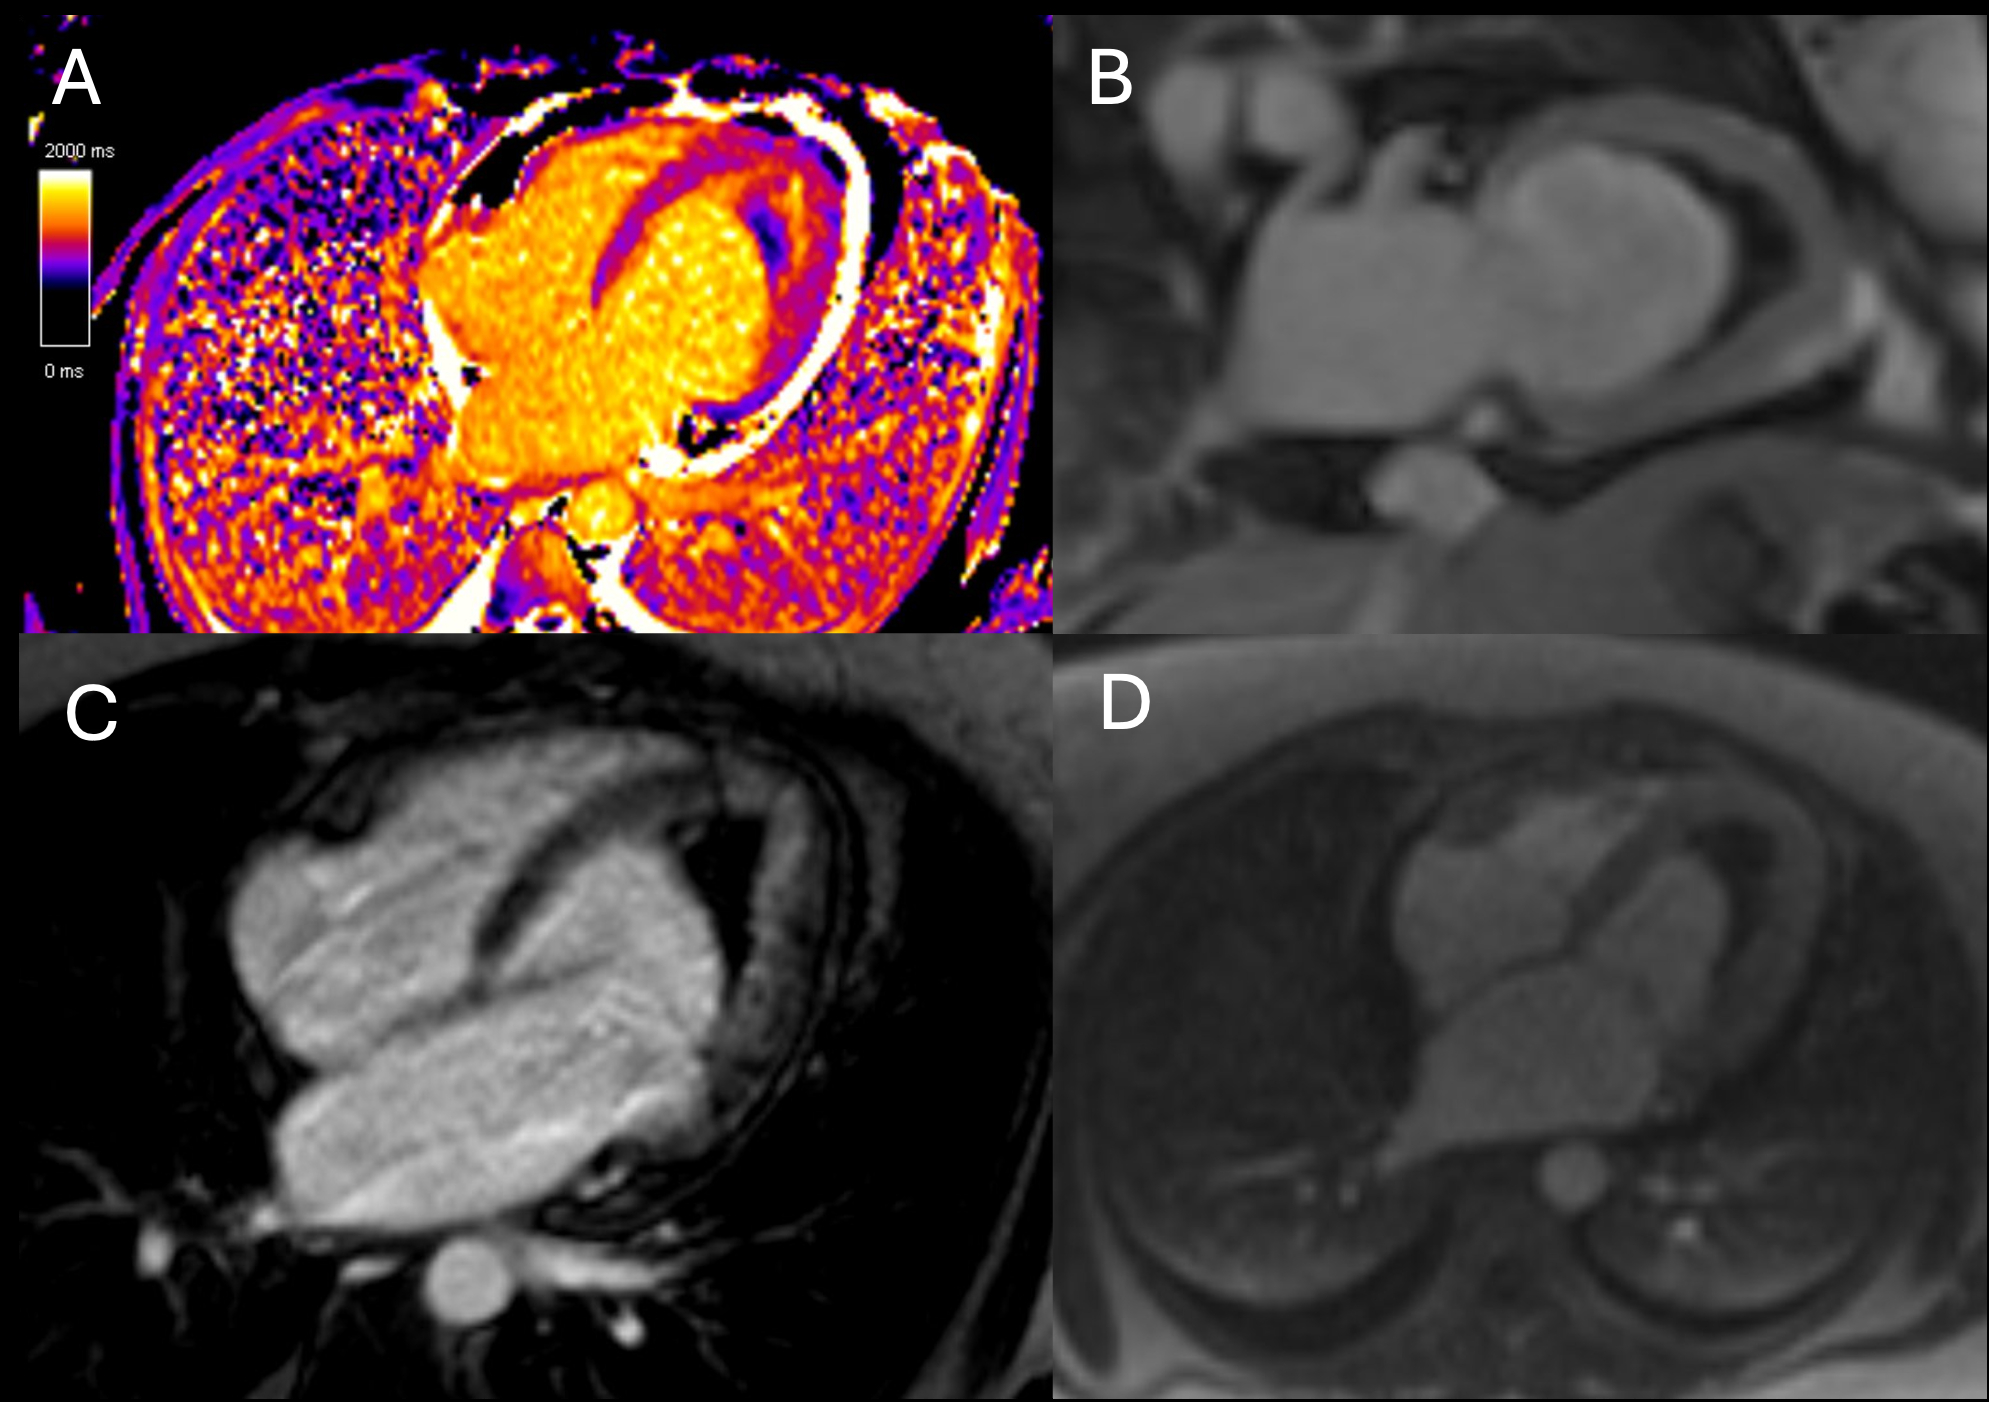

A 37-year-old woman with hypertension, polycystic ovarian syndrome, and a family history of eosinophilic esophagitis presented 8 weeks postpartum with progressive dyspnea and hypoxia. Laboratory testing showed mild eosinophilia and elevated BNP with a normal troponin. Transthoracic echocardiography revealed preserved ejection fraction and apical thickening. Cardiac MRI (1.5T) demonstrated reduced LVEF (43%), mid-to-apical akinesis, and a large laminar apical thrombus (18 × 51 mm). Native T1 and extracellular volume were elevated. First-pass perfusion showed an apical perfusion defect surrounded by hyperenhancing myocardium, consistent with the “double V sign.” Late gadolinium enhancement demonstrated mid-wall fibrosis in the basal anteroseptum. Endomyocardial biopsy revealed only mild myocyte hypertrophy without eosinophilic infiltration.

Eosinophilic myocarditis is an uncommon inflammatory cardiomyopathy that often mimics other etiologies of heart failure and may evade histologic confirmation due to patchy myocardial involvement. In this case, the clinical context and distinct cardiac MRI findings supported the diagnosis despite a non-diagnostic biopsy. Given the imaging and laboratory findings, high-dose corticosteroids and anticoagulation were initiated empirically. At three months, repeat imaging showed improved LVEF (57%), resolution of wall motion abnormalities, and thrombus shrinkage to 7 mm. By ten months, MRI demonstrated normalized systolic function (LVEF 60%), near-complete resolution of the thrombus (10 × 6 mm, tethered in the chordae), and no residual late enhancement. T1 and extracellular volume remained mildly elevated. This case illustrates the diagnostic and longitudinal value of cardiac MRI in eosinophilic myocarditis, particularly when biopsy is inconclusive, and highlights the utility of serial imaging in guiding and monitoring therapy.